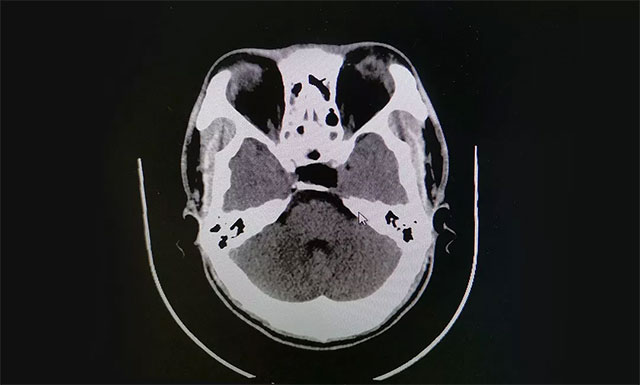

術(shù)后根據(jù)病理分析,該腫瘤為GH腺瘤。術(shù)后患者視物重影已消失,視力明顯改善,目前正在康復(fù)中。

▲ 術(shù)后影像顯示腫瘤被切除